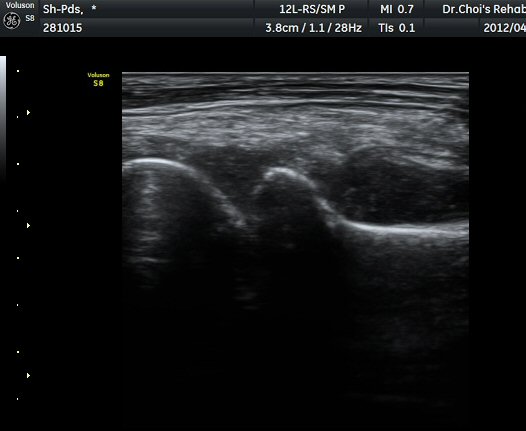

ÆÈ²ÞÄ¡ ÁÖµÎ¿Í Á¾´Ü¸é°Ë»ç À§Ä¡¿¡¼­ ŽÃÊÀÚ ¿ÜÃøÀ¸·Î ÁÖ»ç¹Ù´ÃÀ» »ðÀÔÇÏ¿©

°üÀý³» ÁÖ»çÄ¡·á ½ÃÇà(ÁÖ»ç »çÁø). °üÀý ³» ÁÖ»ç¾×ÀÌ µé¾î°¡´Â °ÍÀÌ ¶Ñ·ÈÈ÷

°üÂûµÇ¾î Áֻ簡 Àß µÇ¾úÀ½À» È®ÀÎÇÒ ¼ö ÀÖ´Ù(ÁÖ»ç µ¿¿µ»ó) .